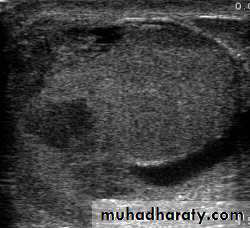

EPIDIDYMO-ORCHITIS

Inflammation confined to the epididymis is epididymitis

Infection spreading to the testis is epididymo-orchitis.

Clinical features

The initial symptoms are those of urinary tract infection.The epididymis and testis swell and become painful.

Fever

The scrotal wall, at first red, oedematous and shiny, may become adherent to the epididymis.

Scrotal U/S